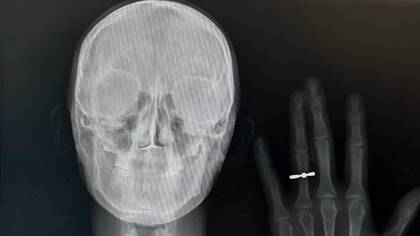

Рентгеновский снимок молодоженов из Новосибирска Кристины Шрайнер и Станислава Ефремова / Фото: Предоставила Кристина Шрайнер

Фото — рентгеновский снимок с рукой и кольцом на безымянном пальце — быстро разлетелось по сети. Оказалось, что так медики решили сообщить своим друзьям о предстоящей помолвке.

В 2023 году такую задумку решилась повторить пара врачей из Владивостока. А недавно подобный снимок сделали и другие молодожены, также преданные медицине, но уже из Новосибирска. Как раз они и прославились в сети.

— Мы оба врачи. Я работаю эндоскопистом, а мой жених Станислав — рентгенологом. Предложение он мне сделал в домашней обстановке. Сообщить родным, которые долго ждали этого события, хотелось красиво. Эта идея показалась нам очень символичной, — рассказывает невеста Кристина Шрайнер.